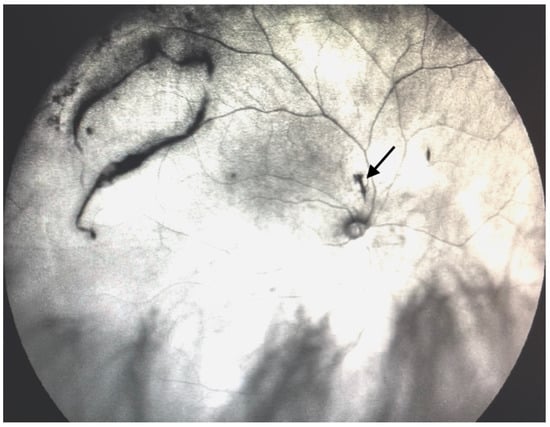

Figure 9.

Ultra-widefield IRcSLO image of an eye with Grade 5 vitreous floaters secondary to vitreous hemorrhage in a patient with history of central retinal vein occlusion that was treated with laser photocoagulation. Dense shadows are observed within the macular area in the primary gaze. See also Video S9.